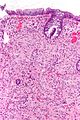

Adrenal Ganglioneuroma. H&E stain. | |

| LM | ganglion cells (large cells with large nucleus and prominent nucleolus), disordered fibrinous-like material, eosinophilic granular bodies |

Microscopic

Features:

- Ganglion cells - key feature.

- Large cells with large nucleus.

- Prominent nucleolus.

- Disordered fibrinous-like material.

- Eosinophilic granular bodies.[3]